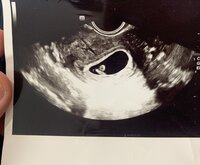

Ultra meni hyvin! Sieltä löytyi pieni kaveri joka vastas viikkoja 5+5 (eli vähän pienempi kuin mitä ite olin laskenu. Sanoi että pienempi ei pitäis olla mutta saattaa olla vähän isompi kun mitä nyt saatiin mitattua) ja hieno sydämen syke!!Onneks oli sydän jo alkanu lyömään koska muuten ois ollu vähän vaikeeta häntä sieltä löytää

Ensimmäinen kuva on tosiaan tämän päivän pikkukaverista vk 5+5 ja alempi esikoisesta 6+6. Onneksi ties mitä etsiä monitorilta niin ei tullut turhaan panikoitua